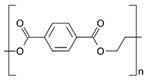

| Polymers | Structure | Fabrication Method | Commercial Products/Literatures | Comments | Reference |

|---|---|---|---|---|---|

| Polycarbonate (PC) |  | Ion-track etching | Estrogen | Excellent stability against oxidation and biodegradation and improves antifouling properties | [151] |

| Polyethylene (PE) |  | Ion-track etching | Catapress (Clonidine), Boehringer IngelheimClimara (Estradiol), Berlex | Physico-chemical stability andordered pore formation with superior membrane performance | [152] |

| Polyethylene terephthalate (PET) |  | Lithography | Ketoprofen | Biostable, antifouling, has better performance of membranes, in useful in preparing surgical meshes and ligaments | [153] |

| Polystyrene (PS) |  | Lithography | d-limonene, ibuprofen | Chemical resistance, easy processing, lower cost, exhibits enhancements in strength, stiffness, toughness, and ductility | [154] |

| PC, PE | - | Ion-track etching | Estraderm (Nitroglycerin), Rotta Research | Cost-effective and biocompatibility is fairly good | [155] |

| PC, PE, PET, PS | - | Phase separation | Deponit (Nitroglycerin), Pharma SchwarzHabitrol (Nicotine), Novartis | Cost-effective and biocompatibility is fairly good | [154,156] |

| Polyurethane (PU) |  | Sol-gel/solvent casting | Vivelle (Estradiol), Novartis | Good elasticity, biodegradable, suitable for hydrophilic drugs, biocompatibility is fairly good | [154] |

| Polysiloxane (silicone) |  | Sol-gel/solvent casting | Prostep (Nicotine), Lederle, Transderm Nitro (Nitroglycerin), AlzaSyncro-Mate-C (Norgestomet) | Better insulation, excellent biocompatibility, and fabricated easily for hydrophilic drugs | [157] |

| Polyisobutylene (PIB) |  | Solvent casting | Aminopyrene, Mitsubishi Petrochem Co., Japan | Good adhesive drug impermeable layer and high degree of tack or self-adhesion | [158] |

| Polymethyl methacrylate (PMMA), poly (2-hydroxy ethyl methacrylate) |  | Layer by layer deposition | Androderm (Testosterone), SmithKline Beecham | Physical strength and transparency | [159] |

| Polyvinyl alcohol (PVA), Poly (ethylene-co-vinyl acetate) |  | Solvent casting | Nitro-Dur I (Nitroglycerin), Key PharmaTestoderm TTS (Testosterone), Alza | Rate-controlling membranes, high membrane permeability, hydrophilicity and strength, suitable for lipophilic drugs | [160] |

| Polyacrylic acid, polyacrylate, polyacrylamide |  | Layer by layer deposition | Epinitril (Nitroglycerin), Rotta ResearchMonsanto (Fentanyl), Dow Corning | Good adhesivity and spreadability and contains a drug impermeable layer | [160] |

| Polylactides (PLA), polylactic-co-glycolic acid (PLGA), polyglycolides (PGA) |  , ,  | Sol-gel/solvent casting | Propranalol, Exxon Chemical Co. | Good biocompatibility; lactic and glycolic acids are the degradation products and they are easily eliminated from the body | [161,162] |

| Polyvinyl pyrrolidone (PVP), poly (N-vinyl pyrrolidone) |  | Sol-gel/solvent casting | Cytarabine, ara-ADA, Polyscience | Superior biocompatibility, has suspension capabilities, antinucleating agent, and enhances release rate | [163] |

| Polyethylene glycol (PEG) | Sol-gel/solvent casting | Miconozale, Rohm, Germany | Chemically inert and free of leachable impurities | [164] | |